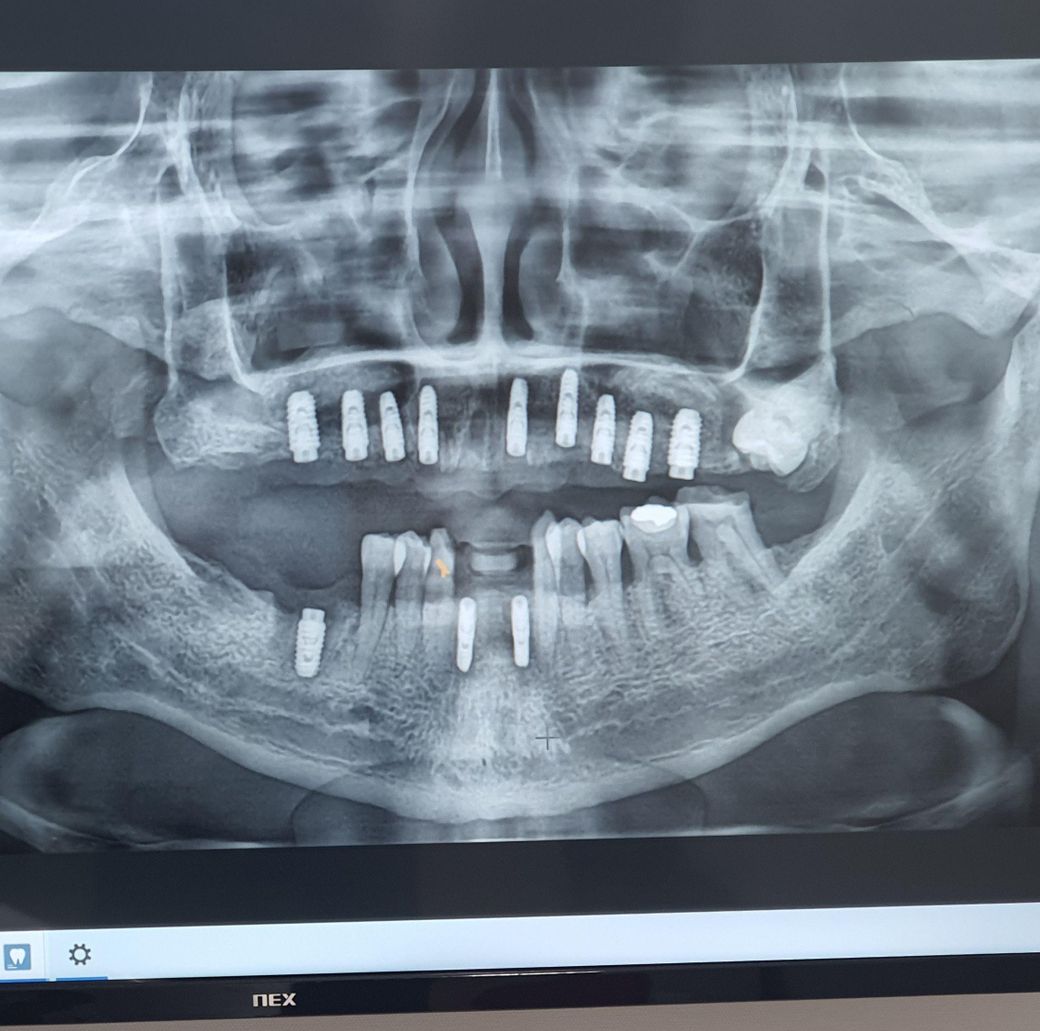

상악동 거상술 4군대하고 한달정도 됐습니다

매복사랑니가 있는대 주치의가 임플란트하는대 영양없다고 통증없으면 안뽑아도 된다고해서 안뽑았거든요.

근대 상악어금니쪽은 잇몸밖에없고 아랫니어금니는 있으니 자꾸 맞다아서 아픈대 뽑아야할까요? 상악동뼈넣은지 한달밖에 안되서 너무걱정되요